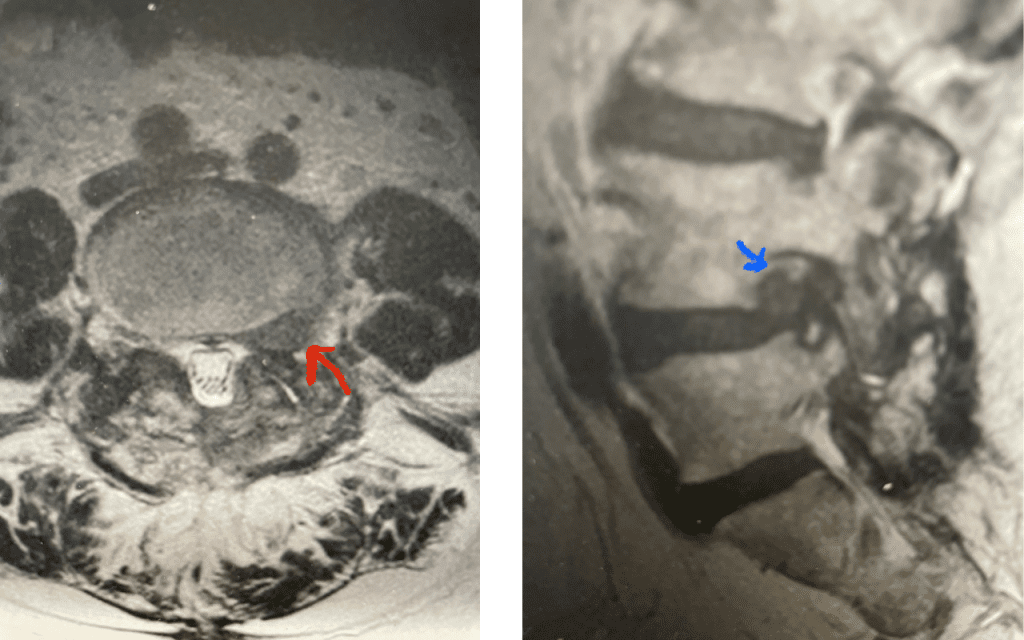

We had a recent flurry of lateral disc herniations. Another challenging case recently was a 76-year-old male who presented with 6 weeks of severe left anterior thigh pain, numbness, and weakness of his hip flexor and quadriceps, four years prior at L4-5 he had a removal of a large L4-5 synovial cyst on the right side of the canal and in situ fusion for which he had done very well. New imaging about a month prior revealed a new large far lateral disc herniation on the left side (Fig 9). The patient had mild spinal stenosis at this level and the cyst gone, but the disc on the left was extraforaminal at L4-5 compressing the left L4 nerve root. He had a trace spondylolisthesis. The patient underwent a series of epidurals with no improvement. Patient agreed to proceed with surgery. The laterality of the disc fragment made it amenable in our opinion for a lateral approach as to attempt a medial approach would be quite risky given the prior laminectomy and attendant scar formation which would increase risk for spinal fluid leak. The prior fusion mass was thin and incomplete and was removed easily with Kerrison punch. The main problem was the scarring in the intertransverse space and discerning the anatomy of the L4-5 facet complex. However, we remained in the “safe zone” and although the nerve was buried in scar tissue was not well identified, we were able to dissect enough to extract the disc fragment. This fragment was clearly pushing upward the scar tissue containing the L4 nerve root. We added an in-situ fusion with BMP because of the slight spondylolisthesis although we had to remove a minimal amount of bone in the safe zone for exposure. Fortunately, the patient had relief from his symptoms.

Fig 9: Axial and Sagittal T2-weighted lumbar MRI demonstrating left L4-5 far lateral disc herniation (red arrow). Notice how on the sagittal MRI the disc herniation fills the foramen and is superiorly oriented, compressing the left L4 nerve root against the L4 pedicle (blue arrow).